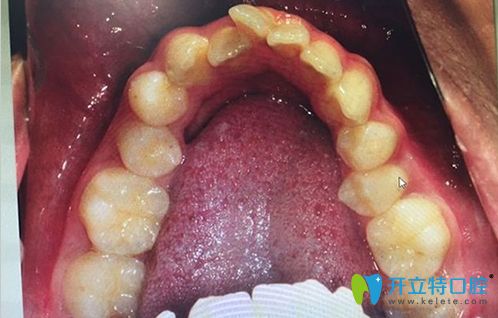

牙弓狹小需要擴(kuò)弓的病例圖

擴(kuò)弓矯正的前后效果對比圖